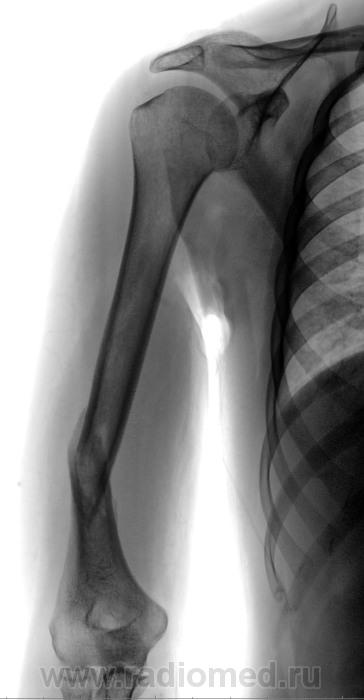

Пол пациента: Мужской пол Тип патологии: Травма Область исследования: Скелетно-мышечная система Методы исследования: Rg Сняли ГИПС, консолидацию ищут... https://radiomed.ru/sites/default/files/styles/case_slider_image/public/user/12/2.201406170044.jpg?itok=gshoRdle ID:39070 Чт, 19/06/2014 - 14:54 #1 Сергей Кузьминов Не на сайте Был на сайте: 1 год 6 месяцев назад Зарегистрирован: 06.10.2012 - 15:51 Публикации: 11813 Здесь её нет.Вторая проекция обязательна. Пт, 20/06/2014 - 10:00 #2 Катенёв Валенти... Не на сайте Был на сайте: 7 лет 6 месяцев назад Зарегистрирован: 22.03.2008 - 22:15 Публикации: 54876 Сергей Кузьминов wrote: Здесь её нет.Вторая проекция обязательна. Вы правы.Приложения: Пт, 20/06/2014 - 14:24 #3 Сергей Кузьминов Не на сайте Был на сайте: 1 год 6 месяцев назад Зарегистрирован: 06.10.2012 - 15:51 Публикации: 11813 Савсем нет консолидации.Давно ли сломано? Пт, 20/06/2014 - 21:06 #4 svetlana292929 Не на сайте Был на сайте: 4 года 1 месяц назад Зарегистрирован: 18.06.2012 - 13:53 Публикации: 869 а угловое смещение не смущает никого? Пт, 27/06/2014 - 10:58 #5 Катенёв Валенти... Не на сайте Был на сайте: 7 лет 6 месяцев назад Зарегистрирован: 22.03.2008 - 22:15 Публикации: 54876 Сергей Кузьминов wrote: Савсем нет консолидации.Давно ли сломано? Сломано 3 месяца тому назад. Пт, 27/06/2014 - 15:05 #6 Сергей Кузьминов Не на сайте Был на сайте: 1 год 6 месяцев назад Зарегистрирован: 06.10.2012 - 15:51 Публикации: 11813 Печально.Наверное, надо было оперировать.

Здесь её нет.Вторая проекция обязательна.

Савсем нет консолидации.Давно ли сломано?

а угловое смещение не смущает никого?

Сломано 3 месяца тому назад.

Печально.Наверное, надо было оперировать.